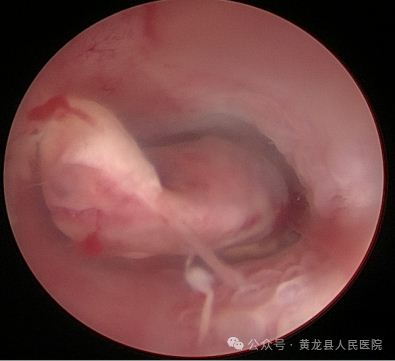

经宫腔镜宫腔粘连分离术+宫腔镜子宫内膜息肉切除术。

患者赵某,58岁,绝经后B超提示子宫内膜增厚8天。患者合并高血压,高血脂、盆腔炎,入院后给予降压、调脂、抗感染治疗后行宫腔镜检查术,术中见宫腔中上部可见一纤维状粘连,宫底及双侧输卵管开口不可见,宫腔下段前后壁分别可见一枚赘生物,大小约1×0.2cm、0.5×0.2cm,实施宫腔镜宫腔粘连分离术及宫腔镜子宫内膜息肉切除术,术后病检:子宫内膜息肉。

术前宫腔术后宫腔